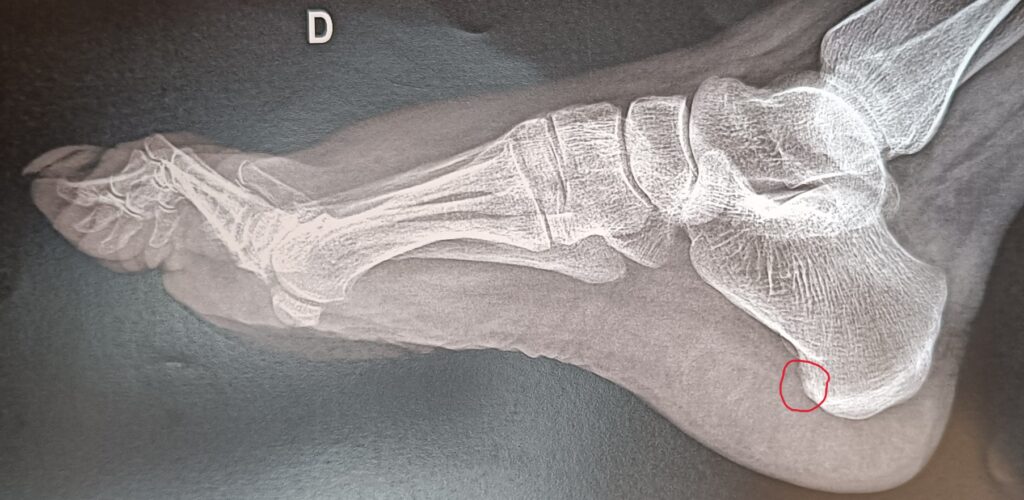

Radio

Une simple radiologie montre l’exostose en forme d’épine de rosier sur l’os du talon = calcanéum.